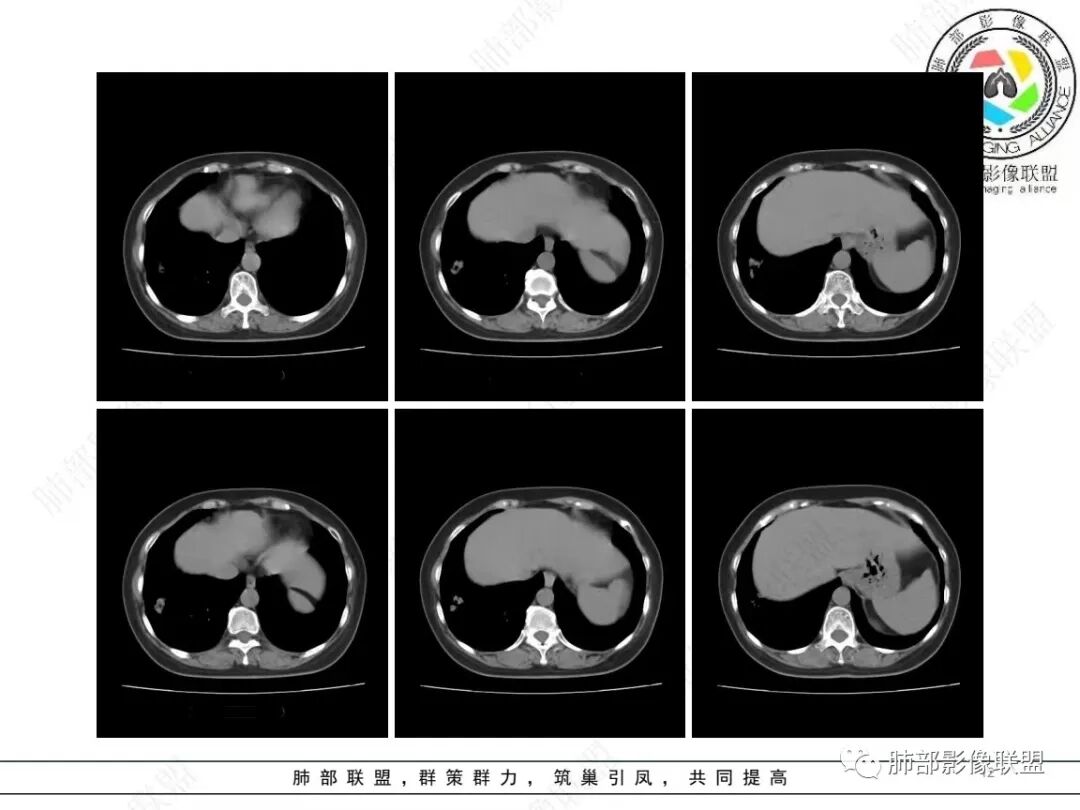

1、临床特点:58岁女性,体检发现右肺结节7天,无基础病,中性粒细胞百分比略高,无实验室检查无特殊。

2、影像特点:右肺下叶胸膜下不规则结节,矢状位整体病灶沿着支气管方向呈斑片状,不均匀强化。病灶边缘多平直、凹陷(从部分层面可见极其像月牙铲),缺乏膨隆感,周围可见多发长索条影,病灶内可见多发充气支气管影,大部分支气管完全贯通病灶并轻度扩张,极少支气管进入病灶内堵塞,观察横断位视频、部分层面病灶周围可见边界欠清的ggo。纵隔窗病灶内未见明显钙化影。未见卫星病灶及树芽征。

3、综合分析:中老年女性胸膜下不规则结节,无特殊临床表现,实验室检查亦无特殊,病灶在部分断面呈斑片状,边缘多平直甚至凹陷,缺乏分叶及膨隆感,未见粗短毛刺及胸膜凹陷,部分层面似见”月牙铲“样外形,但缺乏张力的“月牙铲”不太可靠。灶周磨玻璃晕也会让人警惕肺腺癌可能,磨玻璃影边界是否清晰常须薄层仔细分辨。

实性密度为主结节影,支气管密切相关,边缘多平直,缺乏分叶膨隆感,缺乏张力,有磨玻璃晕但边界不清。更符合慢性炎性病变。

病理提示隐球菌感染可能。肺部隐球菌感染孤立性病灶与肺腺癌的鉴别诊断是个永恒的话题。